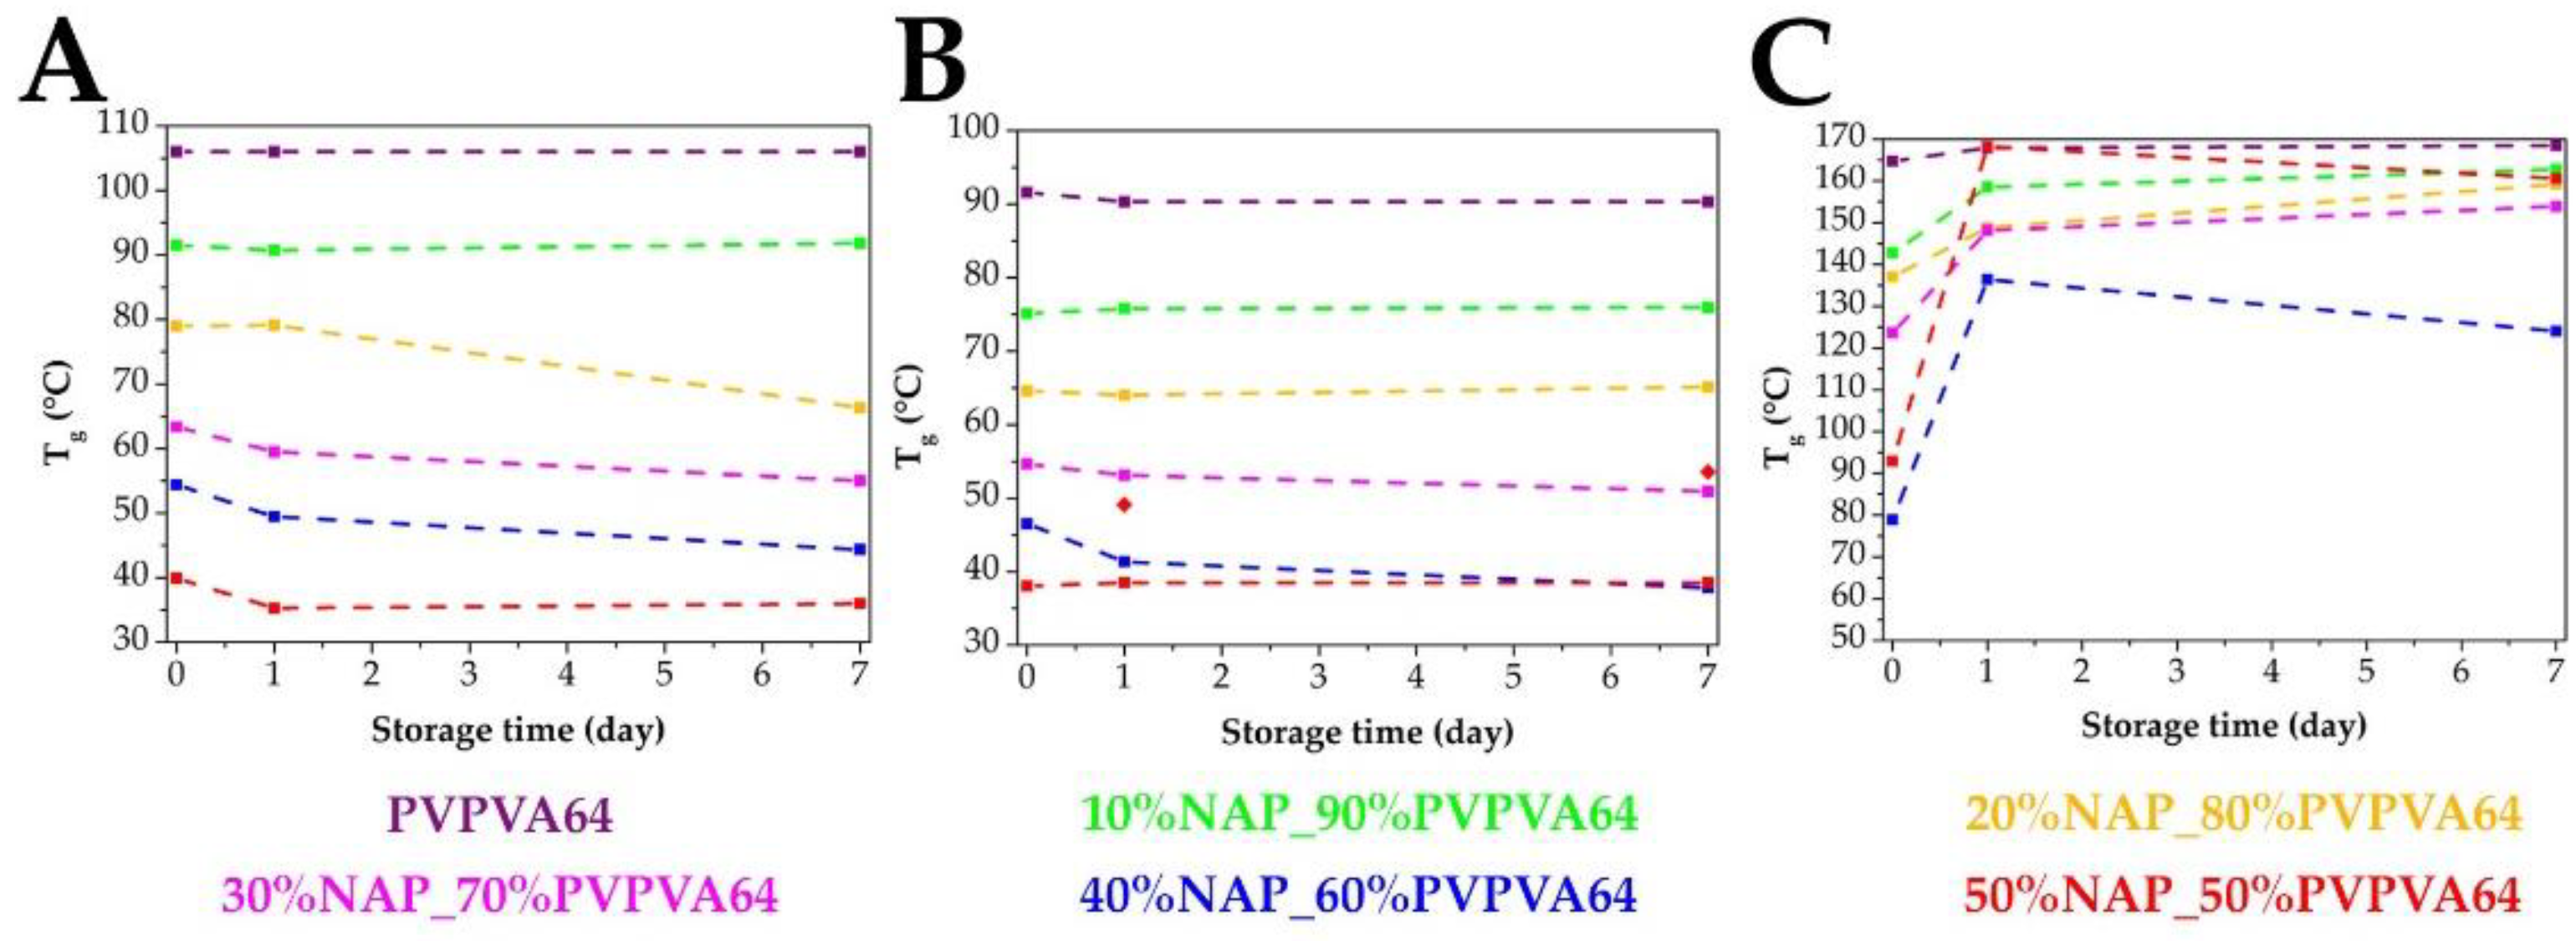

3.2. Measuring the Glass Transition Temperature with Different Methods

3.3. Effect of the Stress Stability Tests

3.4. Correlations between the Measured Tg Values and the Stability